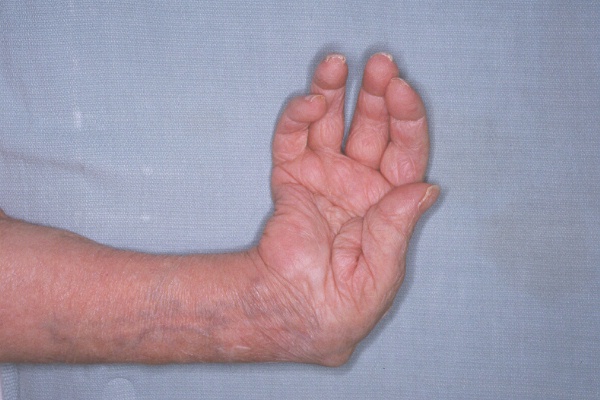

Clinical Example: Rheumatoid arthritis

rheumatoid hand